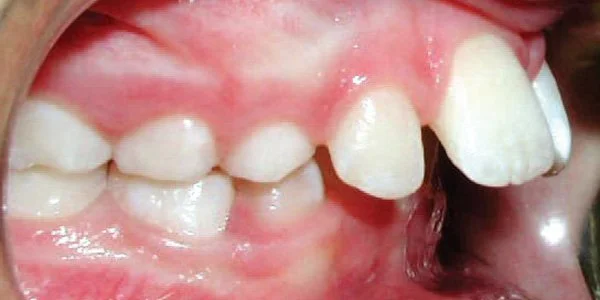

Protrusion

Upper teeth stick out beyond the lower teeth.